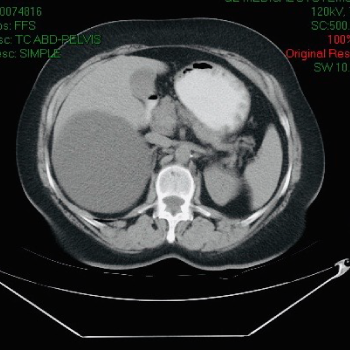

Quistes en el Hígado

Los quistes en el hígado son los tumores benignos muy frecuentes. Son bolsitas con agua que salen dentro del hígado. La mayor parte de las veces no producen ningún problema, pero en otras ocasiones los quistes en el hígado pueden ser por cáncer, Infecciones o estar producidos por parásitos.